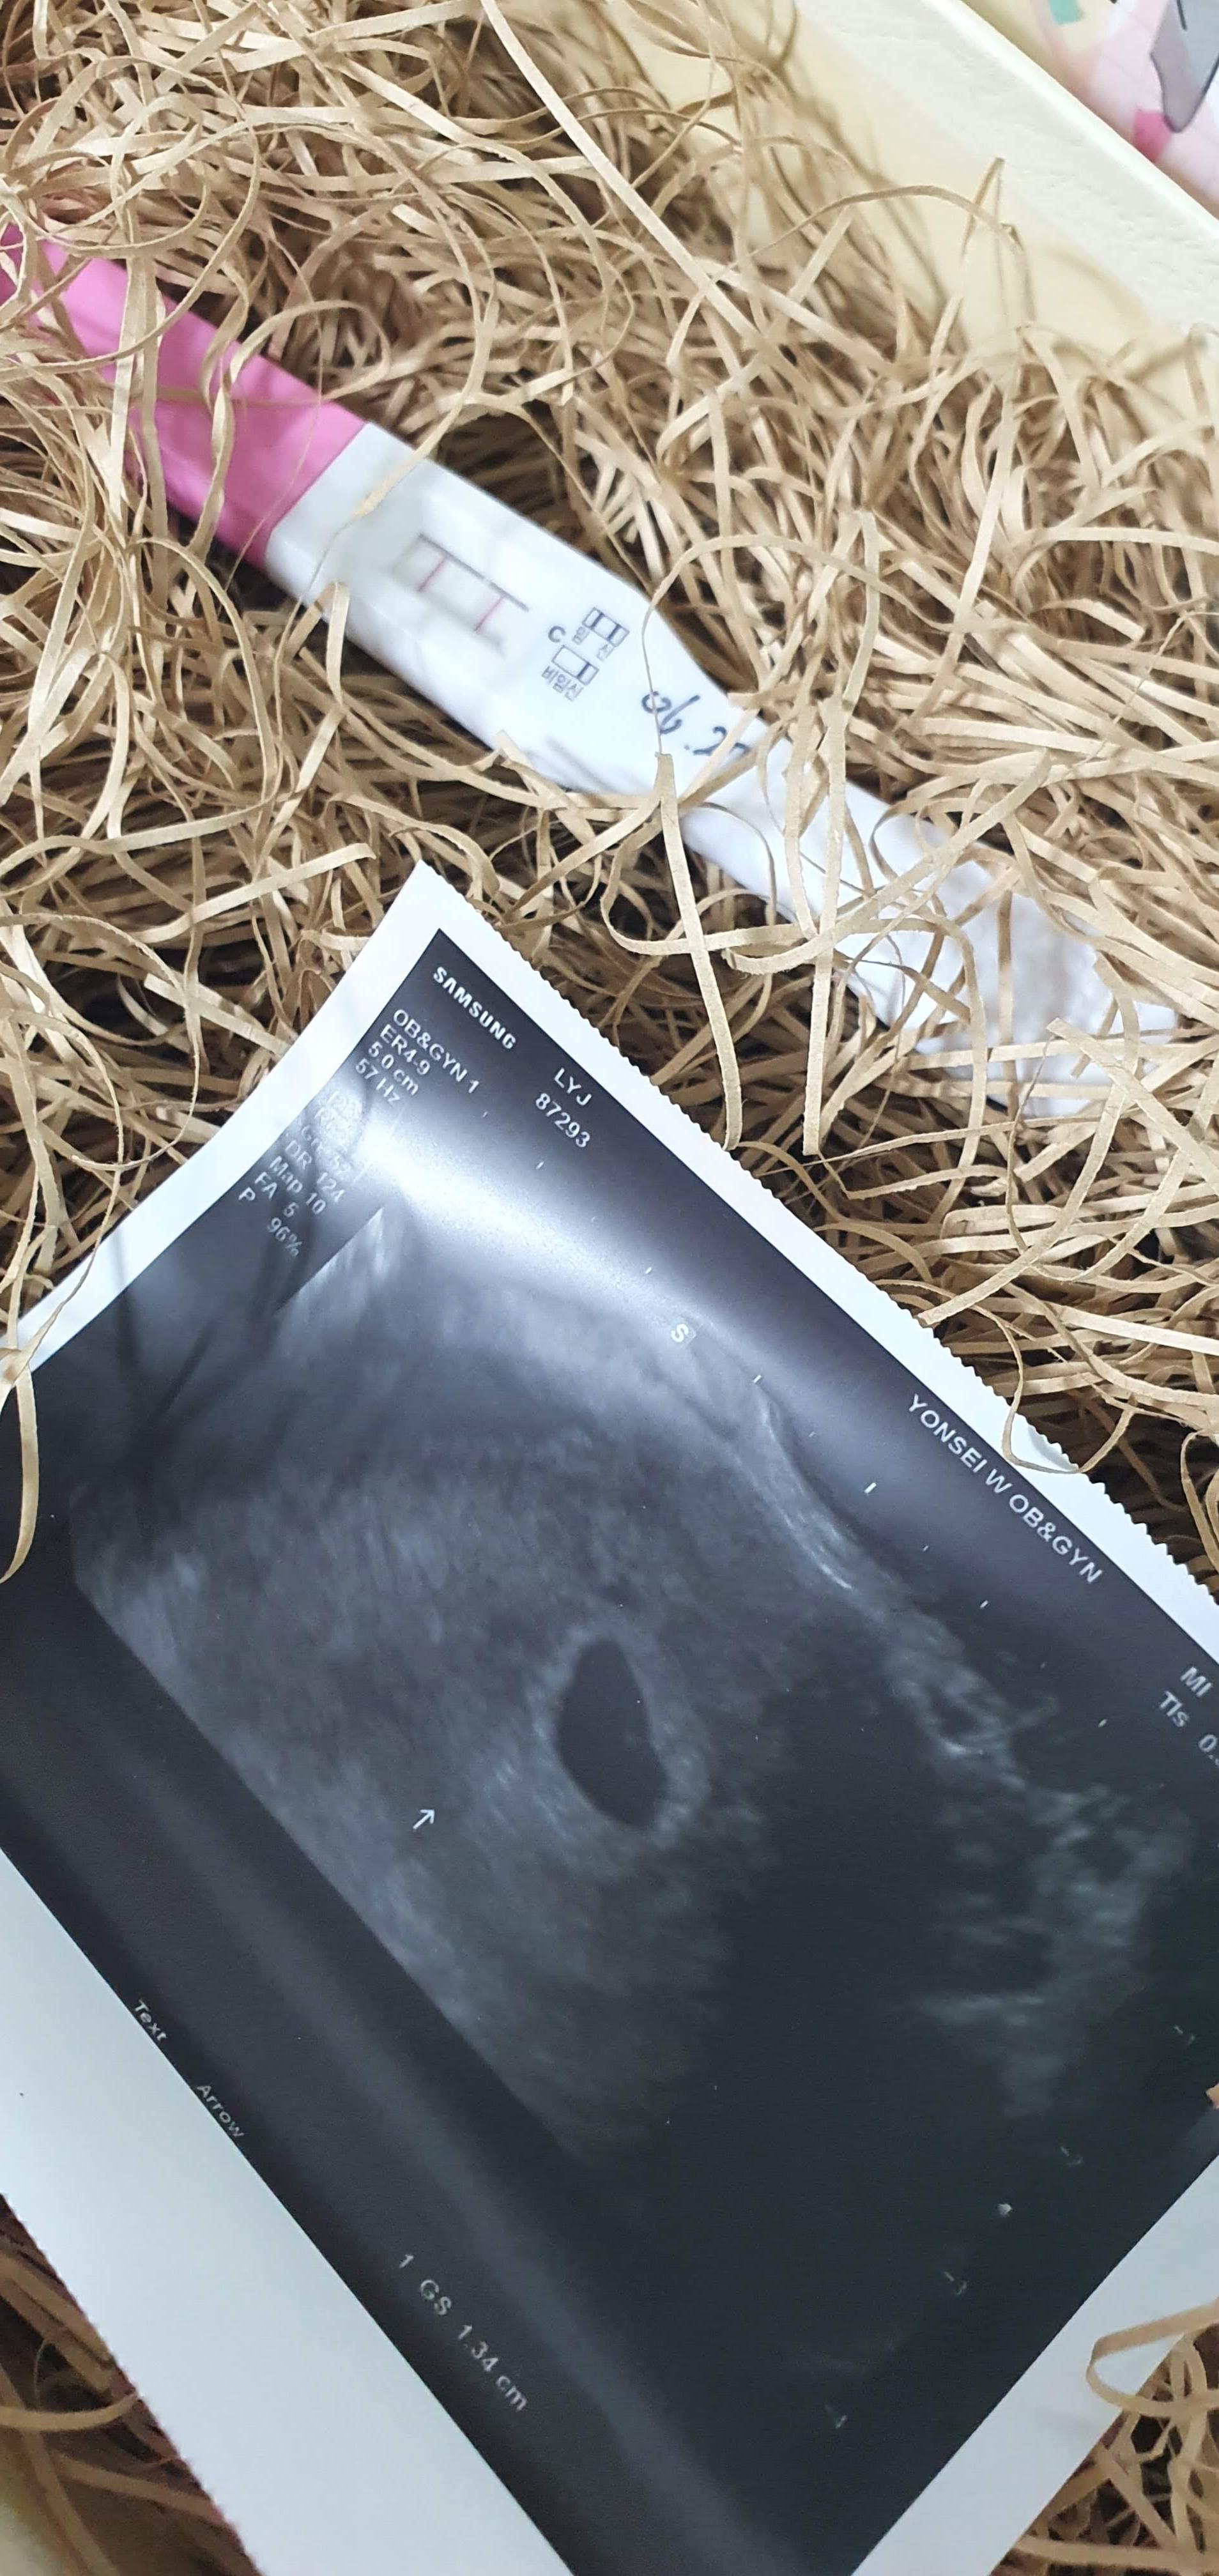

당연히 임테기는 넣어뒀고

젤 먼저 찍었던 소듕한 초음파 사진을 넣었음.

자세히 봐야알 수 있게 쏚쏚

수풀 속에 숨기는 센스도, 히힣.

아, 이거 초음파 ㅋㅋ

ㅋㅋㅋㅋ 정말 임산부 아님 잘 알기 힘둘꺼다..

저 동그란 애기집 안에 있는 동그란 점이

내 뱃속의 버피다..

하이, 버피.